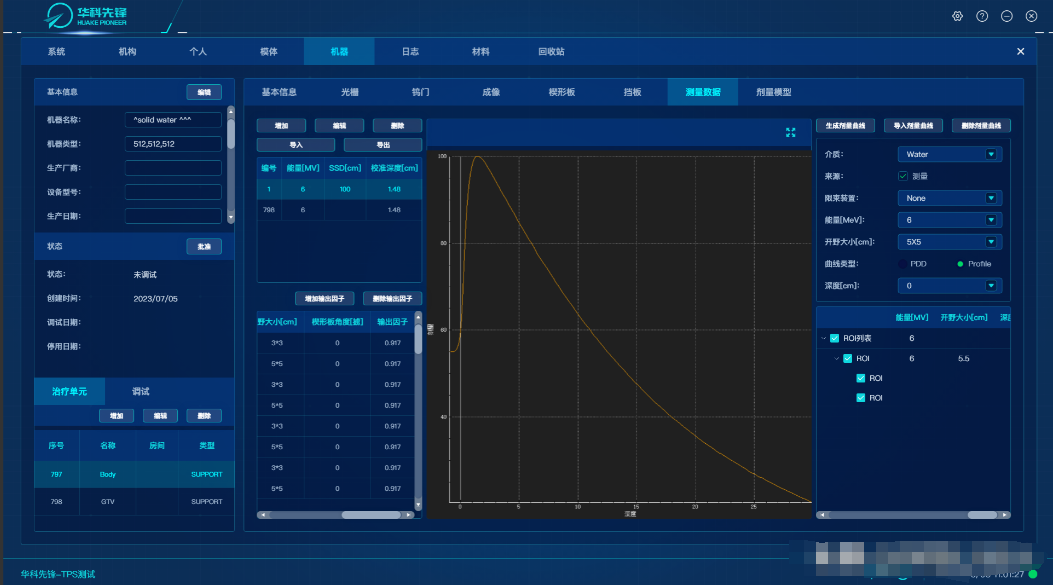

三、医学影像存档与通信系统(PACS)的作用

医学影像存档与通信系统(PACS)是专门用于医学影像管理的系统,它可以实现医学影像的采集、存储、传输、显示和处理等功能。

在影像采集方面,PACS 系统可以与各种医学影像设备进行连接,如 CT、MRI、超声等,实现影像的自动采集和传输。在影像存储方面,系统可以将采集到的影像存储在服务器中,实现长期保存和管理。在影像传输方面,系统可以通过网络将影像传输到医生工作站、手术室、会诊室等,方便医生进行诊断和治疗。在影像显示方面,系统可以提供高清晰度的影像显示功能,方便医生进行观察和分析。在影像处理方面,系统可以对影像进行各种处理,如增强、滤波、测量等,为医生提供更多的诊断信息。

PACS 系统的作用主要体现在以下几个方面:首先,提高了影像诊断的效率和准确性。医生可以通过系统快速查看影像信息,避免了传统胶片的繁琐和错误。同时,系统还可以提供影像对比、三维重建等功能,帮助医生更好地进行诊断。其次,方便了影像的存储和管理。影像可以存储在服务器中,不会因为时间和空间的限制而丢失。同时,系统还可以对影像进行分类、归档等管理,方便查询和使用。再次,促进了医疗信息的共享和交流。PACS 系统可以与其他医疗信息系统进行对接,实现医疗信息的共享和交流。医生可以通过系统查看患者的病历记录、检查检验报告等,为诊断和治疗提供参考。最后,有助于医疗质量的控制和管理。PACS 系统可以对影像的质量、诊断的准确性等进行监控和管理,提高医疗质量和安全。